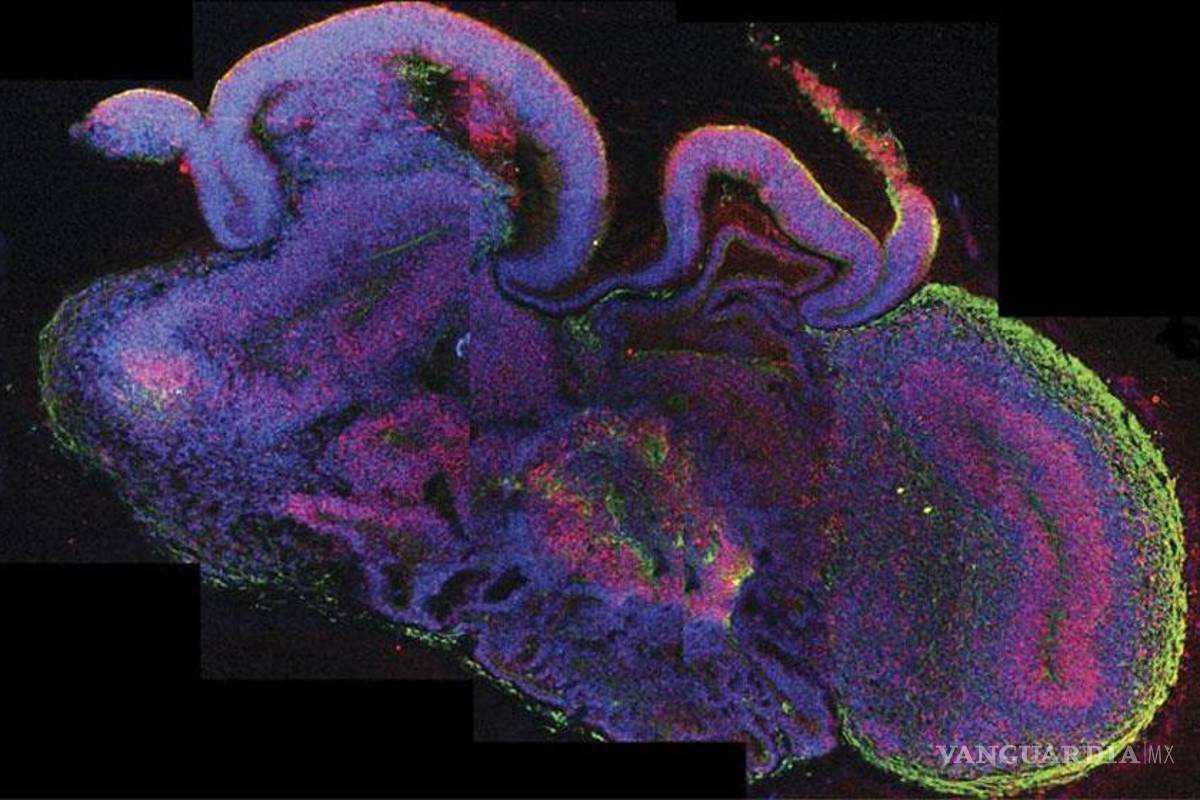

Londres, Inglaterra.- Un equipo de científicos europeos ha desarrollado pequeños cerebros humanos tridimensionales, de cuatro milímetros de diámetro, a partir de células madre pluripotentes que ayudarán a profundizar en el estudio de las enfermedades neurológicas, informó hoy la revista científica "Nature".

Estos órganos artificiales, fruto de una investigación conjunta de la Universidad de Bonn (Alemania) y el Instituto de Biotecnología Molecular de Viena (Austria), aportan importantes avances sobre el desarrollo del cerebro durante las etapas más tempranas y sus patologías.

Estos microcerebros, que incluyen la corteza cerebral que cubre los dos hemisferios, están formados por diferentes tejidos dispuestos en capas, cuya organización guarda muchas semejanzas con la de un cerebro en sus etapas más tempranas de desarrollo.